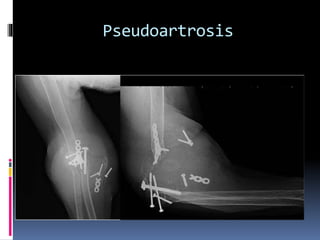

Este documento trata sobre las fracturas del tercio distal del húmero. Brevemente describe que representan el 0-5% de todas las fracturas, que la mayoría son del tipo C, y que pueden causar lesiones de tejidos blandos y nervios. Explica que en niños la línea de fractura suele ser supracondilea. Además, cubre temas como la anatomía relevante, mecanismos de lesión, clínica, diagnóstico, clasificación, y tratamiento quirúrgico y conservador de estas fracturas.